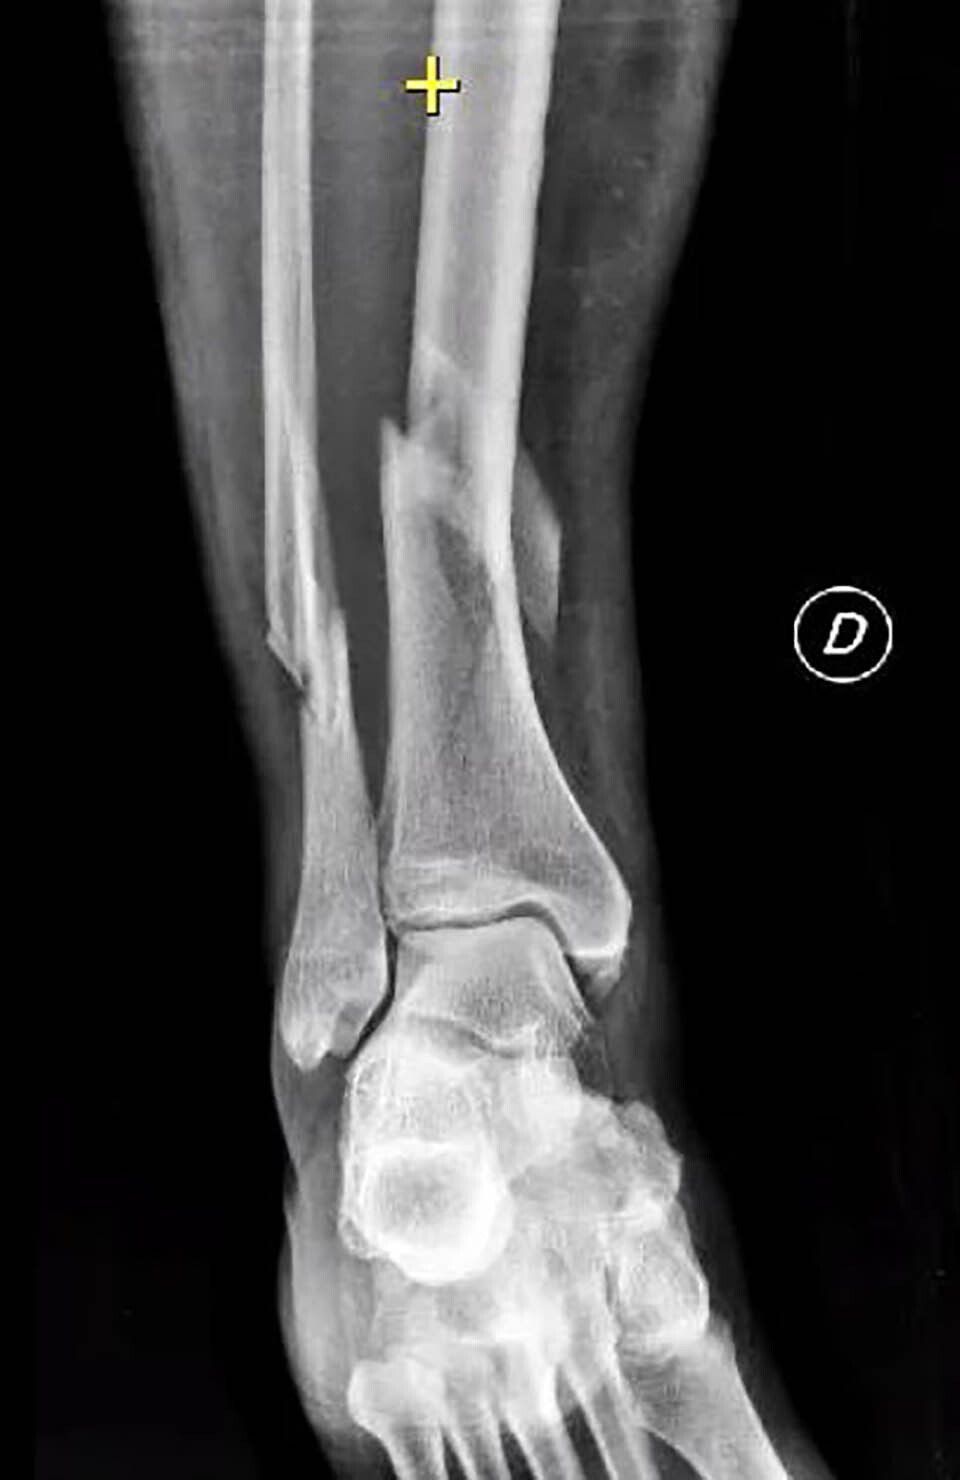

Pseudoarthrosis can be radiographically classified as atrophic or hypertrophic. The former is associated with poor vascular supply, and the latter with a lack of mechanical stability. In atrophic pseudoarthrosis, there are few signs of bone apposition, sometimes there may be resorption of the ends, and usually, the bone segment is mobile.

In hypertrophic pseudoarthrosis, there is an increase in bone callus at the fracture site, with signs of consolidation without complete healing, and usually, there is less mobility.

Other bones, like the femoral head, talus, and scaphoid, have limited blood supply. In these cases, a fracture can cause a disruption in the vascular system, increasing the risk of pseudoarthrosis.

Finally, other bones, like the tibia, have moderate blood supply as they are covered by a thin layer of soft tissues. Severe trauma can compromise both internal and external vascularisation, increasing the risk of pseudoarthrosis.